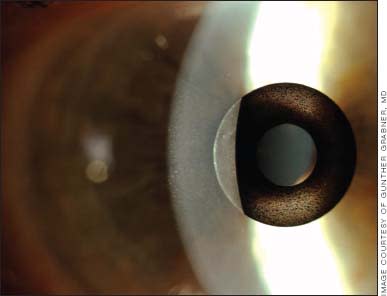

AcuFocus says the Kamra inlay, which is implanted monocularly in the non-dominant eye in a few minutes in a laser suite, is smaller than a contact lens and looks like a black ring. A tiny aperture or hole is in the center of the inlay. The inlay works by blocking unfocused light and allowing only focused light to reach the retina. AcuFocus explains that when light rays are focused, a person may have a wider range of vision at near, intermediate and distance.

A rendering of the Kamra corneal inlay as it looks in the eye. The Kamra inlay is implanted monocularly in the non-dominant eye.